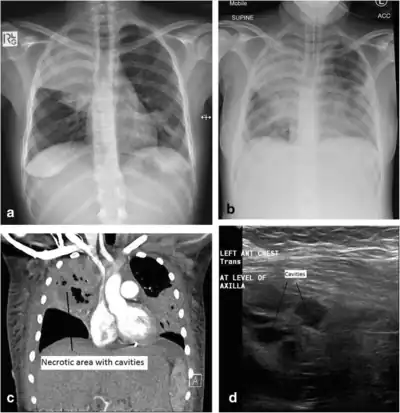

a) Initial plain chest radiograph showing a dense right upper zone airspace opacity and lingula airspace changes, consistent with multi-focal pneumonia. The following images were performed 24 h later. b) Plain chest radiograph with the patient intubated and ventilated revealing cavitation in the right mid to upper zones, pleural effusion and more general airspace changes bilaterally. c) Computed tomography (CT) scan, coronal view, demonstrating non-enhancing area (necrotic) thin-walled cavities within the right upper lobe and lingula. d) Lung ultrasonographic image displaying thin-walled cavities in the lingula region of the left lung. And this needs even more clarification.[note 1]